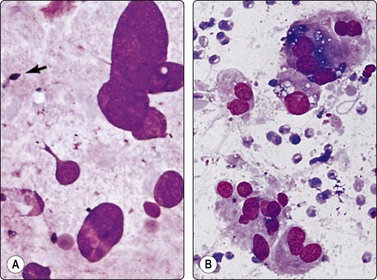

Inadvertent aspiration of the seminal vesicle may yield large atypical cells that may mislead the unwary into an erroneous diagnosis of poorly differentiated carcinoma. Large hyperchromatic, often multilobated, pleomorphic, even bizarre, nuclei are seen.9,36,37 Coarse intracytoplasmic granules of lipofuscin, which stain dark green–blue with DQ, brown with Pap or H&E, quite different from the secretory granules of prostate epithelium (Figs 13.12 and 13.13), dense aggregates of basophilic amorphous material and spermatozoa in the background indicate origin from seminal vesicle.

image

Fig. 13.12 Seminal vesicle epithelium

(A) Large bizarre nuclei; note occasional spermatozoa in the background (arrow) (DQ, HP); (B) Single epithelial cells with large pleomorphic nuclei; note coarse intracytoplasmic pigment (DQ, HP).

image image

Fig. 13.13 Seminal vesicle epithelium

(A) Vaguely glandular aggregates of epithelial cells with pleomorphic and hyperchromatic nuclei; abundant cytoplasm with vacuoles and brown pigment granules (Pap, HP); (B) Corresponding tissue section (H&E, HP).